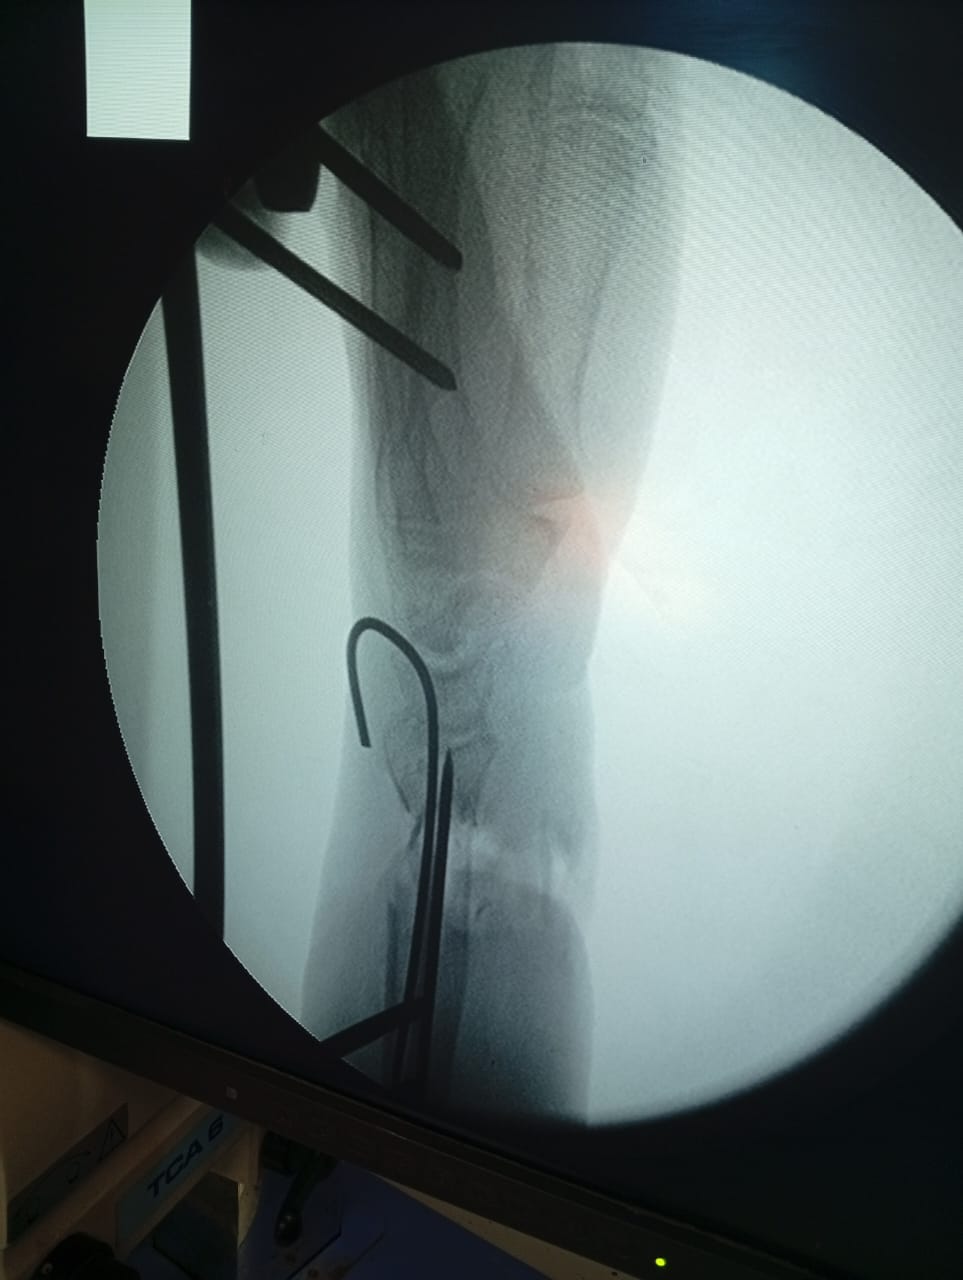

وأكدت الدكتورة نيفين شعبان، وكيل وزارة الصحة بالفيوم، أن مستشفى الفيوم العام بقيادة الدكتور محمد عبد الله، استقبل الحالة وهي تعاني من تهتك شديد بالجلد، وقطع كامل بالأعصاب والأوتار في منطقة الرسغ، مع تأثر بالغ بالدورة الدموية لليد، نتيجة كسر مضاعف بعظام الساعد، ما شكّل تهديدًا حقيقيًا بفقدان اليد.

وبدأ التدخل الجراحي بقيام فريق جراحة العظام بتثبيت الكسر المضاعف بدقة عالية، لضمان استقرار العظام وتهيئة الحالة لاستكمال التدخل الجراحي الدقيق، ثم تولى فريق جراحة التجميل إجراء جراحة ميكروسكوبية معقدة، شملت: إصلاح الأعصاب المصابة، إعادة توصيل الأوتار المقطوعة، تحسين الدورة الدموية للرسغ واليد، وذلك بهدف الحفاظ على اليد ومنع بترها، والعمل على استعادة وظيفتها الحركية قدر الإمكان.